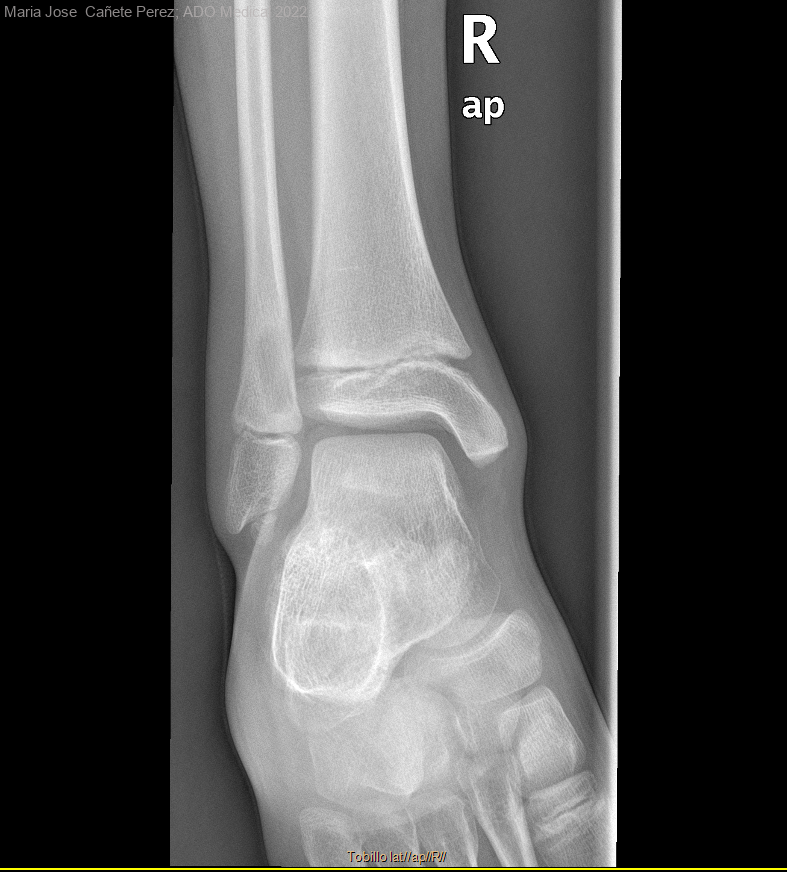

Niño de 9 años que acude a cita previa por dolor de tobillo derecho sin traumatismo previo de una semana de evolución, a la exploración se observa dolor a la palpación, se le pide RX donde se halla...